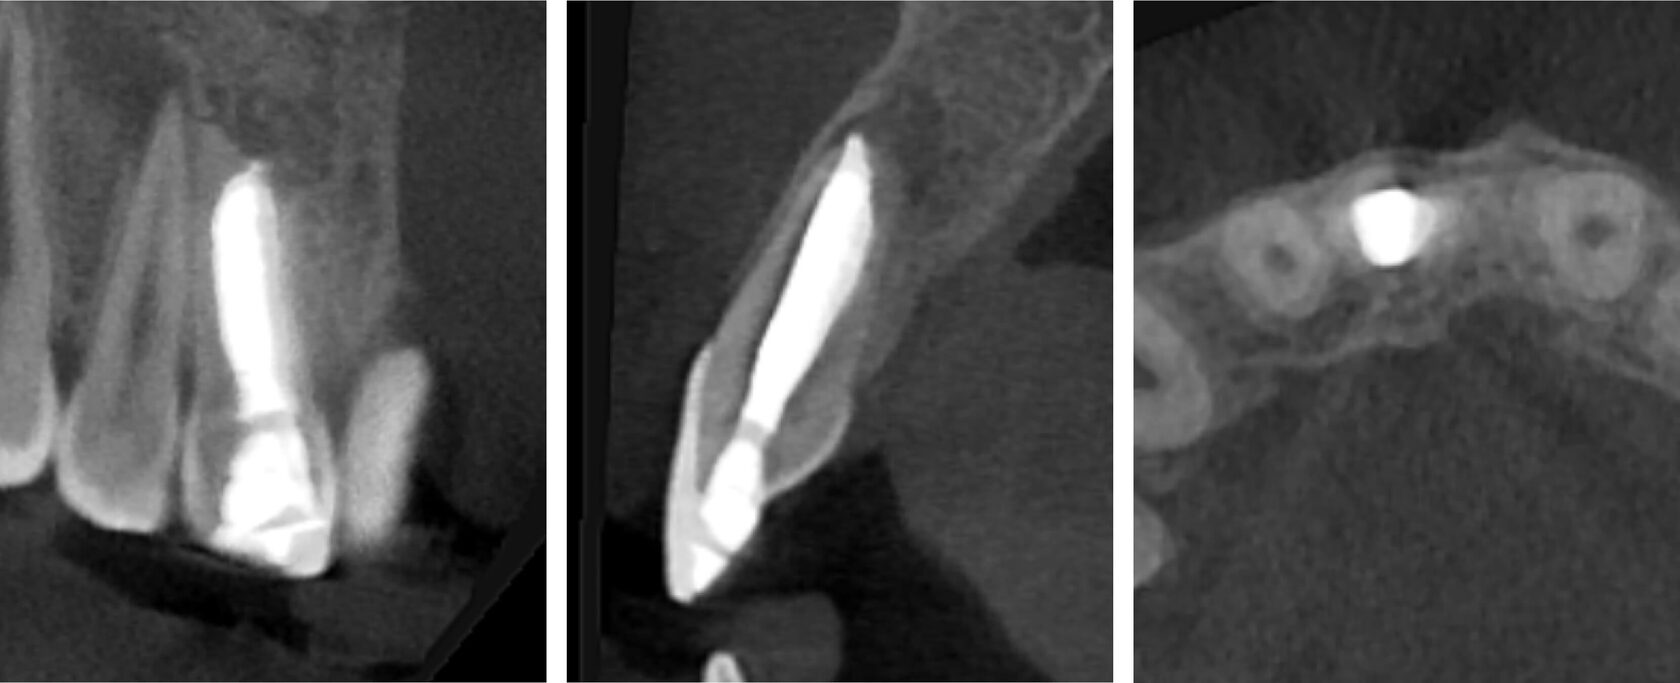

2. Зуб 11 девитален, апикальный периодонтит с обширной деструкцией костной ткани, зуб 12 витален. (Фото 2,3,4)

5. Контрольный осмотр через 7 месяцев, восстановление костной ткани, зуб 12 витален. (Фото 11,12,13)